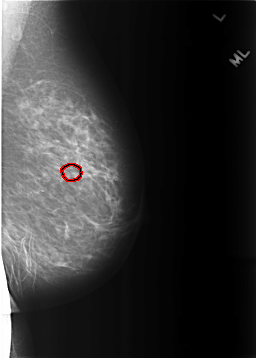

C_0288_1.LEFT_MLO

LEFT_MLO LINES 5720 PIXELS_PER_LINE 4088 BITS_PER_PIXEL 12 RESOLUTION 50 OVERLAY

FILE: C_0288_1.LEFT_MLO.OVERLAY

TOTAL_ABNORMALITIES 1

ABNORMALITY 1

LESION_TYPE CALCIFICATION TYPE PLEOMORPHIC DISTRIBUTION CLUSTERED

ASSESSMENT 4

SUBTLETY 4

PATHOLOGY BENIGN

TOTAL_OUTLINES 1

BOUNDARY